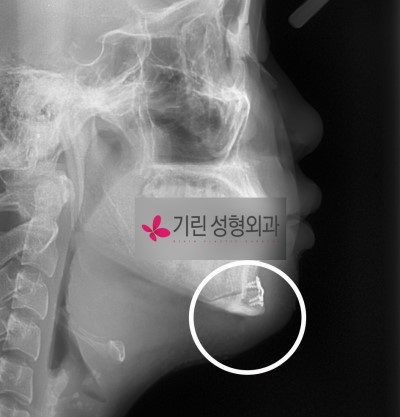

수술후엑스레이

![턱의 길이를 줄여주는 턱끝수술[앞턱길이줄임술] 관련 이미지 4](https://pub-9f2bb3498faf4d1d8714b41df24753e3.r2.dev/content/clinics/archive/pr7y376obf/naver_blog/girinlife/assets/by_hash/19977b2c1edadb80f9bd09b53191aea7e8f68eaaeeb17e24f554a29e02025140.jpg)

이처럼 재수술의 위험성을 최소한으로 줄이기 위해 앞턱수술 즉 절골은 반드시 필요한 경우에만 시행합니다. 위 사례처럼 턱이 길어서 경미한 주걱턱처럼 보이는 경우에는 사각턱수술만으로는 교정의 어려움이 있기 때문에 티절골이 병행됩니다. 그렇지 않고 단지 앞턱넓이가 넓다는 이유로 티절골을 하는 것은 바람직하지 않으며 대부분 앞턱끝까지 절골하는 긴곡선절제술을 적용합니다.